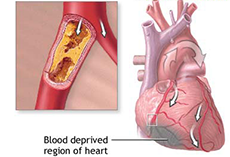

冠状动脉粥样硬化性心脏病

疾病介绍:冠状动脉粥样硬化性心脏病是冠状动脉血管发生动脉粥样硬化病变而引起血管腔狭窄或阻塞,造成心肌缺血、缺氧或坏死而导致的心脏病,常常被称为“冠心病…【详细】